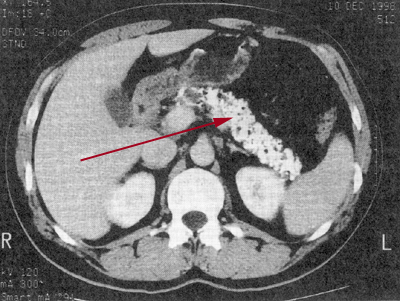

Picture of a computerised tomography (CAT Scan) or a sketch show a enlarged pancreatic duct in the body of the pancreas, with calcination.

Calcification (arrow) with a chronic pancreatitis.